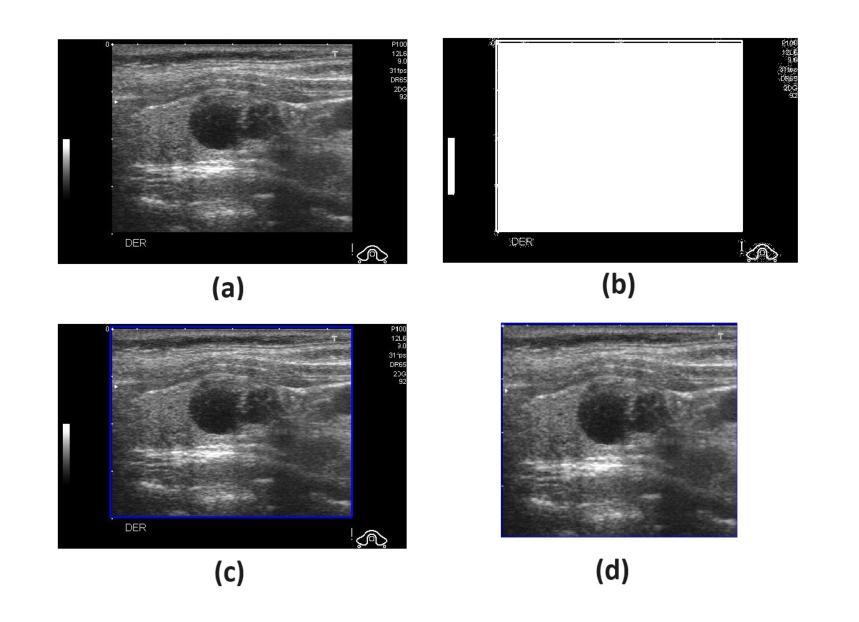

In this study, we develop a new CAD system for accurate thyroid cancer classification with emphasis on feature extraction. Prior studies have shown that thyroid texture is important for segregating the thyroid ultrasound images into different classes. Based upon our experience with breast cancer classification, we first conjuncture that the Discrete Cosine Transform (DCT) is the best descriptor for capturing textural features. Thyroid ultrasound images are particularly challenging as the gland is surrounded by multiple complex anatomical structures leading to variations in tissue density. Hence, we second conjuncture the importance of localization and propose that the Local DCT (LDCT) descriptor captures the textural features best in this context. Another disadvantage of complex anatomy around the thyroid gland is scattering of ultrasound waves resulting in noisy and unclear textures. Hence, we third conjuncture that one image descriptor is not enough to fully capture the textural features and propose the integration of another popular texture capturing descriptor (Improved Local Binary Pattern, ILBP) with LDCT. ILBP is known to be noise resilient as well. We term our novel descriptor as Binary Pattern Driven Local Discrete Cosine Transform (BPD-LDCT). Final classification is carried out using a non-linear SVM. The proposed CAD system is evaluated on the only two publicly available thyroid cancer datasets, namely TDID and AUITD. The evaluation is conducted in two stages. In Stage I, thyroid nodules are categorized as benign or malignant. In Stage II, the malignant cases are further sub-classified into TI-RADS (4) and TI-RADS (5). For Stage I classification, our proposed model demonstrates exceptional performance of nearly 100% on TDID and 97% on AUITD. In Stage II classification, the proposed model again attains excellent classification of close to 100% on TDID and 99% on AUITD.